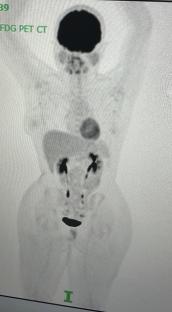

Eventually, her persistence paid off, and she was referred to Hammersmith Hospital for a .

The scan revealed she had , a type of that starts in white blood cells called lymphocytes.

Following her diagnosis, Zee said she had six months of at Hammersmith Hospital, but it turned out to be unsuccessful.

Zee said: “Sadly, the lymphoma had returned in my neck, chest, and liver. I was absolutely devastated. The doctors said they didn’t expect this.